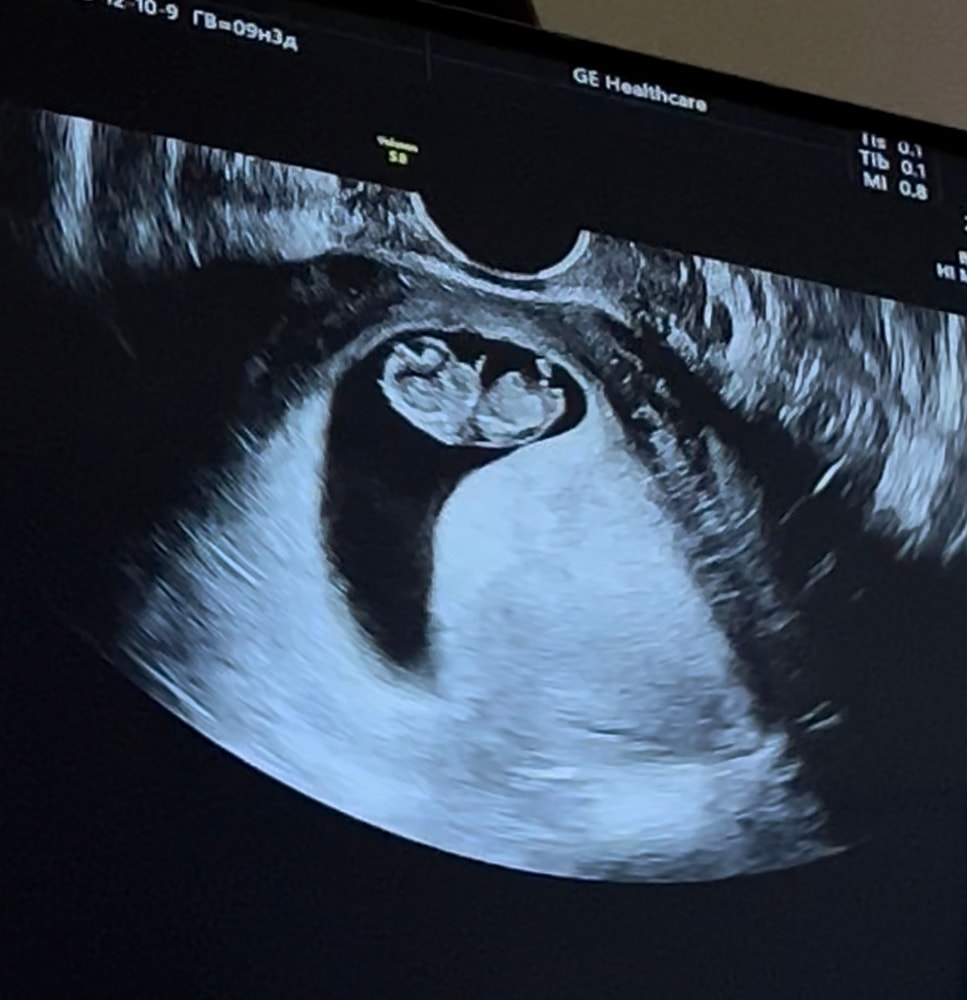

По месячным 9.3 - по узи 9.2

Растем😍 Теперь ждём первый скрининг!

Ктр 25 мм

ЧСС 168